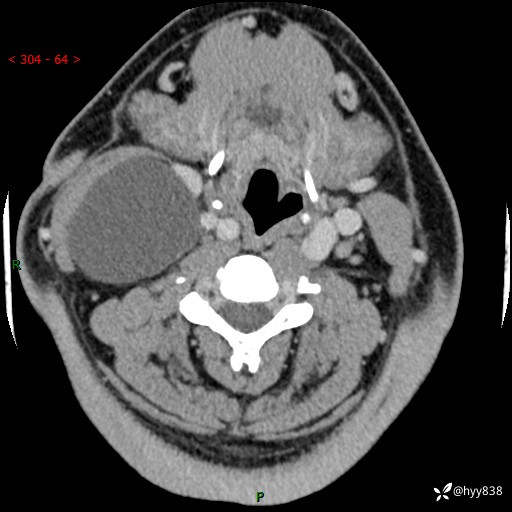

颈部CT平扫+增强